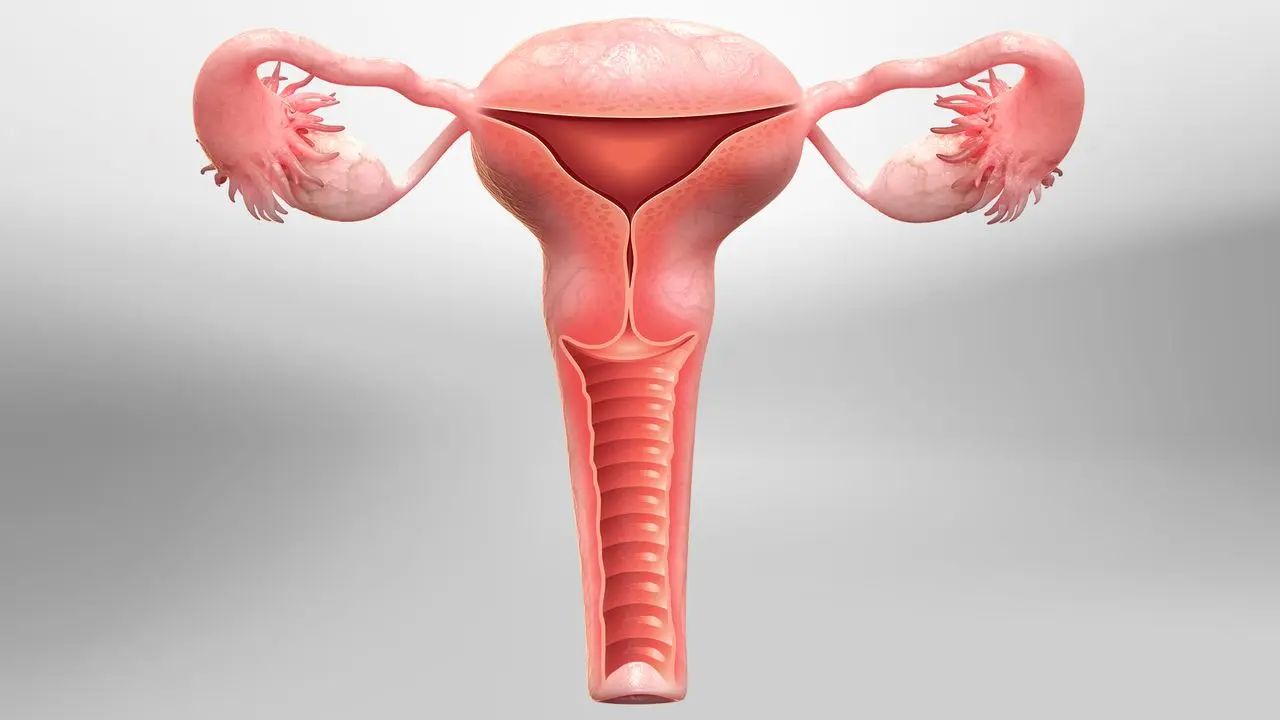

Hysterectomy

A hysterectomy is a surgical procedure to remove the uterus, offering long-term relief from chronic gynecological issues such as fibroids, heavy bleeding, or pelvic pain.